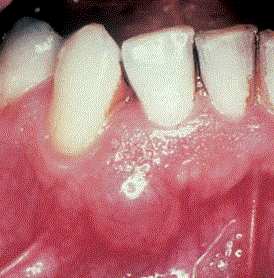

Gingivazyste im anterioren Unterkiefer, Regio 42–43.